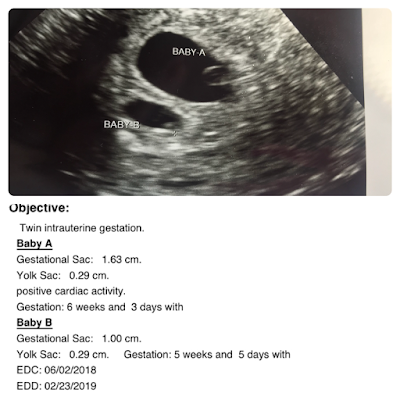

The ultrasound tech inserted the wand, and I quickly caught a glimpse of a sac... then two sacs. The image was so quick, I couldn't check off my mental check list of fetal pole, yolk sac and heart fluttering. She got the wand in better position, and I saw one sac only. She measured it and 6 weeks 3 days. She was surprised because at the time, I was only❤️ 5 weeks 6 days. She maneuvered the wand, and the second sac I thought I had initially seen showed up. It measured and looked much smaller which worried me. The ultrasound tech said this is actually what it should be measuring because I was only 5 weeks 6 days. Baby B measured a day behind at 5 weeks 5 days. Baby A did have a visible heart movement (fluttering), but baby B didn't. The ultrasound tech did not seem too concerned though as I was not even 6 weeks technically yet.

She asked us to come back on July 9th to see how babies were doing. We are crossing my fingers baby B's heart is fluttering at that time too!